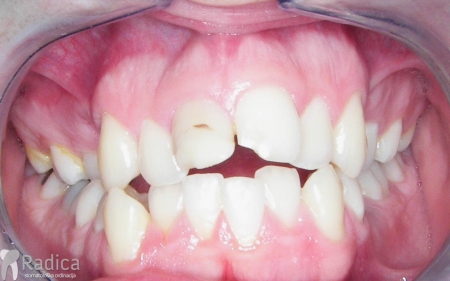

Slučaj 2: ispravljanje kompresije Invisalign full terapijom- u ovom slučaju je izvađen jedan donji sjekutić